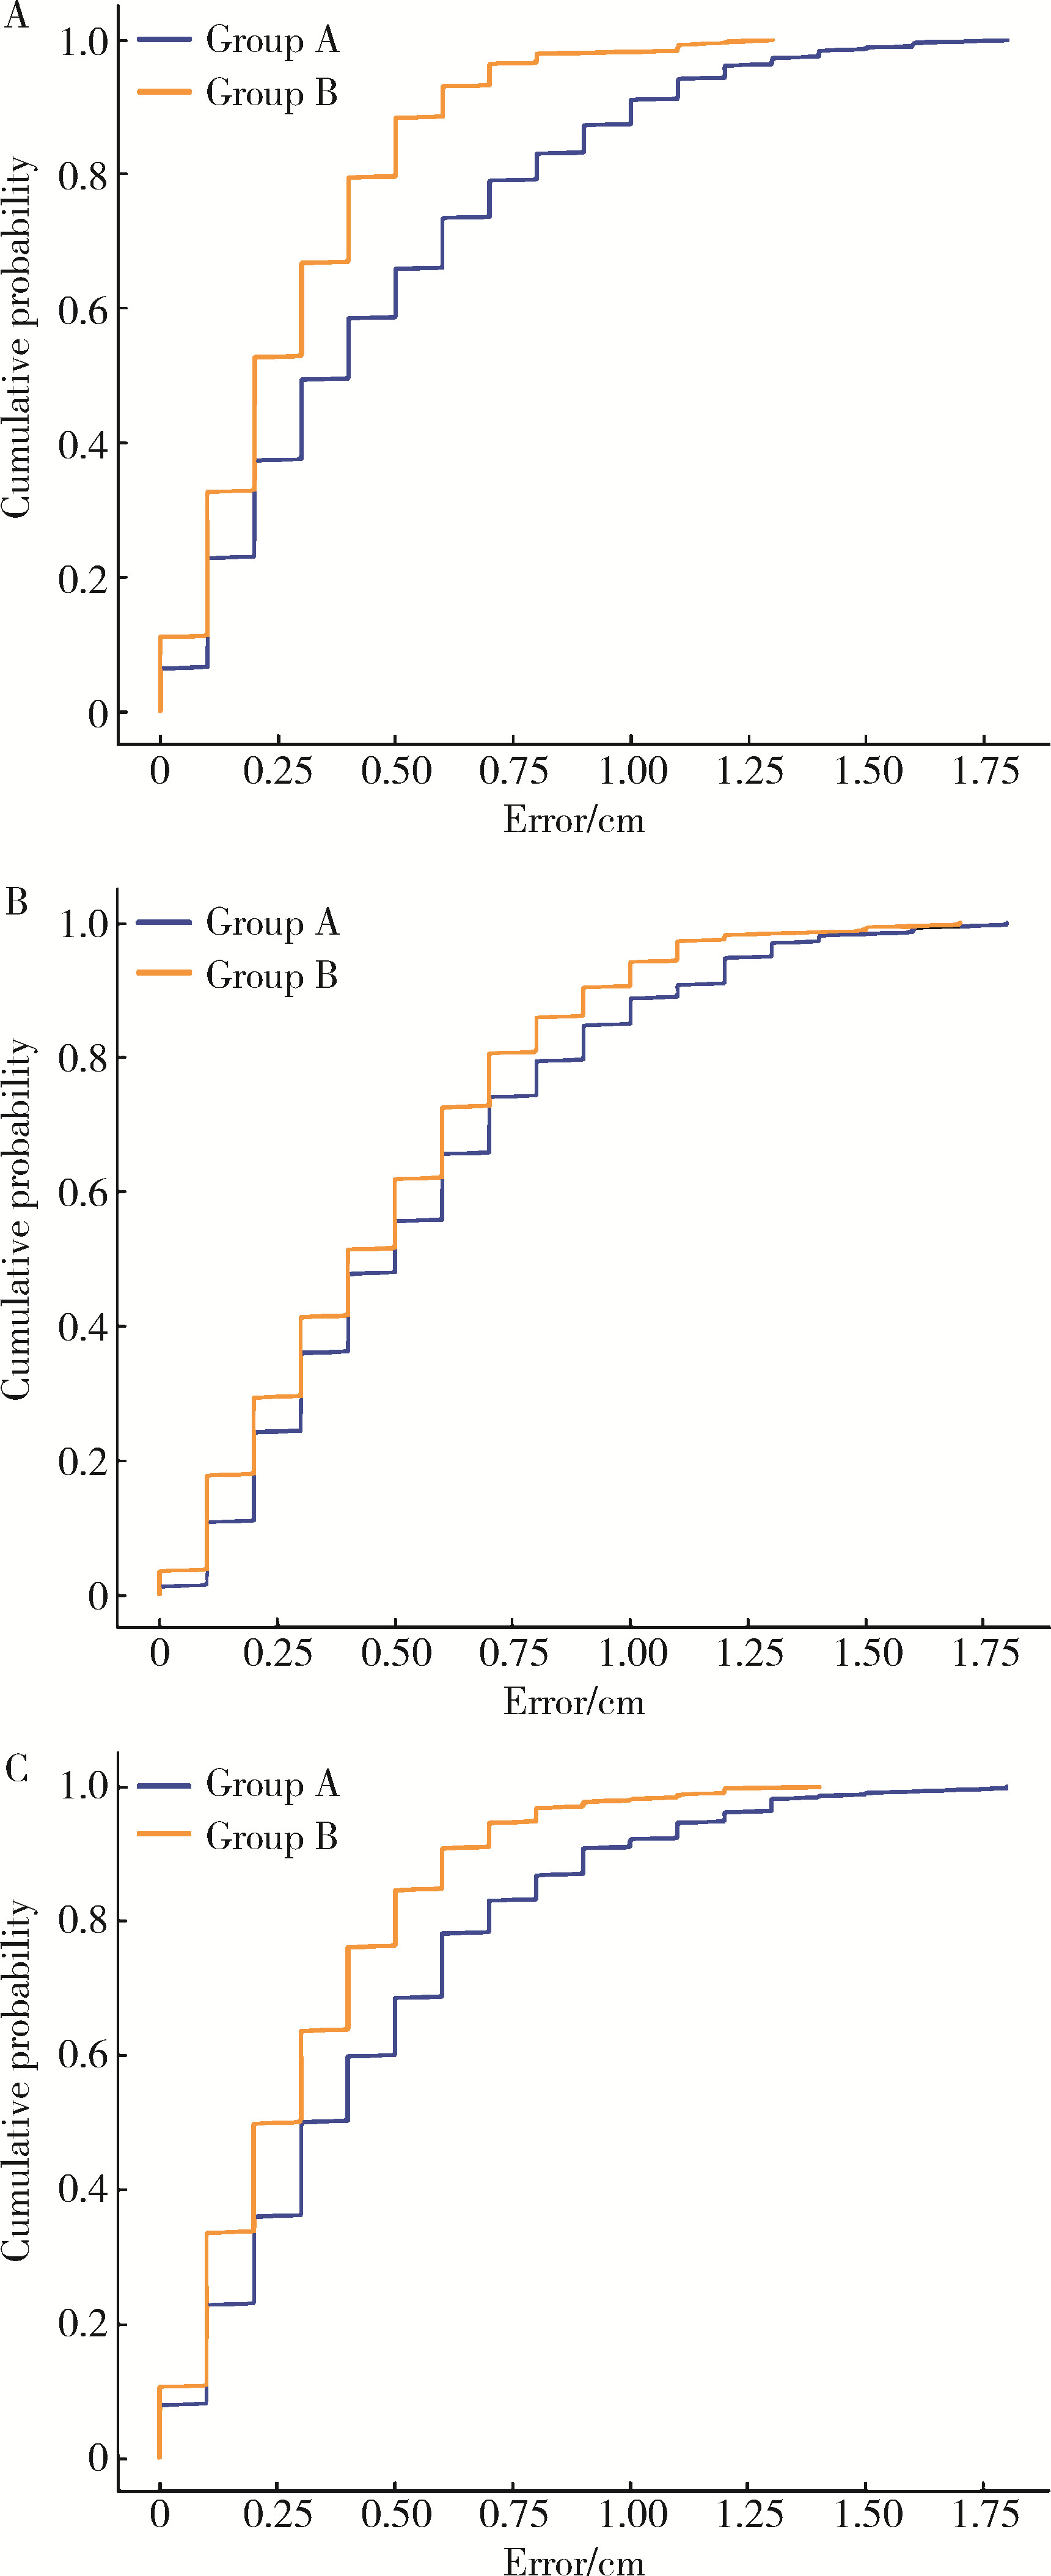

Comparison of setup errors between two immobilization methods in prostate cancer radiotherapy based on cone-beam computed tomography

- Department of Radiation Oncology, Peking University First Hospital, Beijing 100034, China